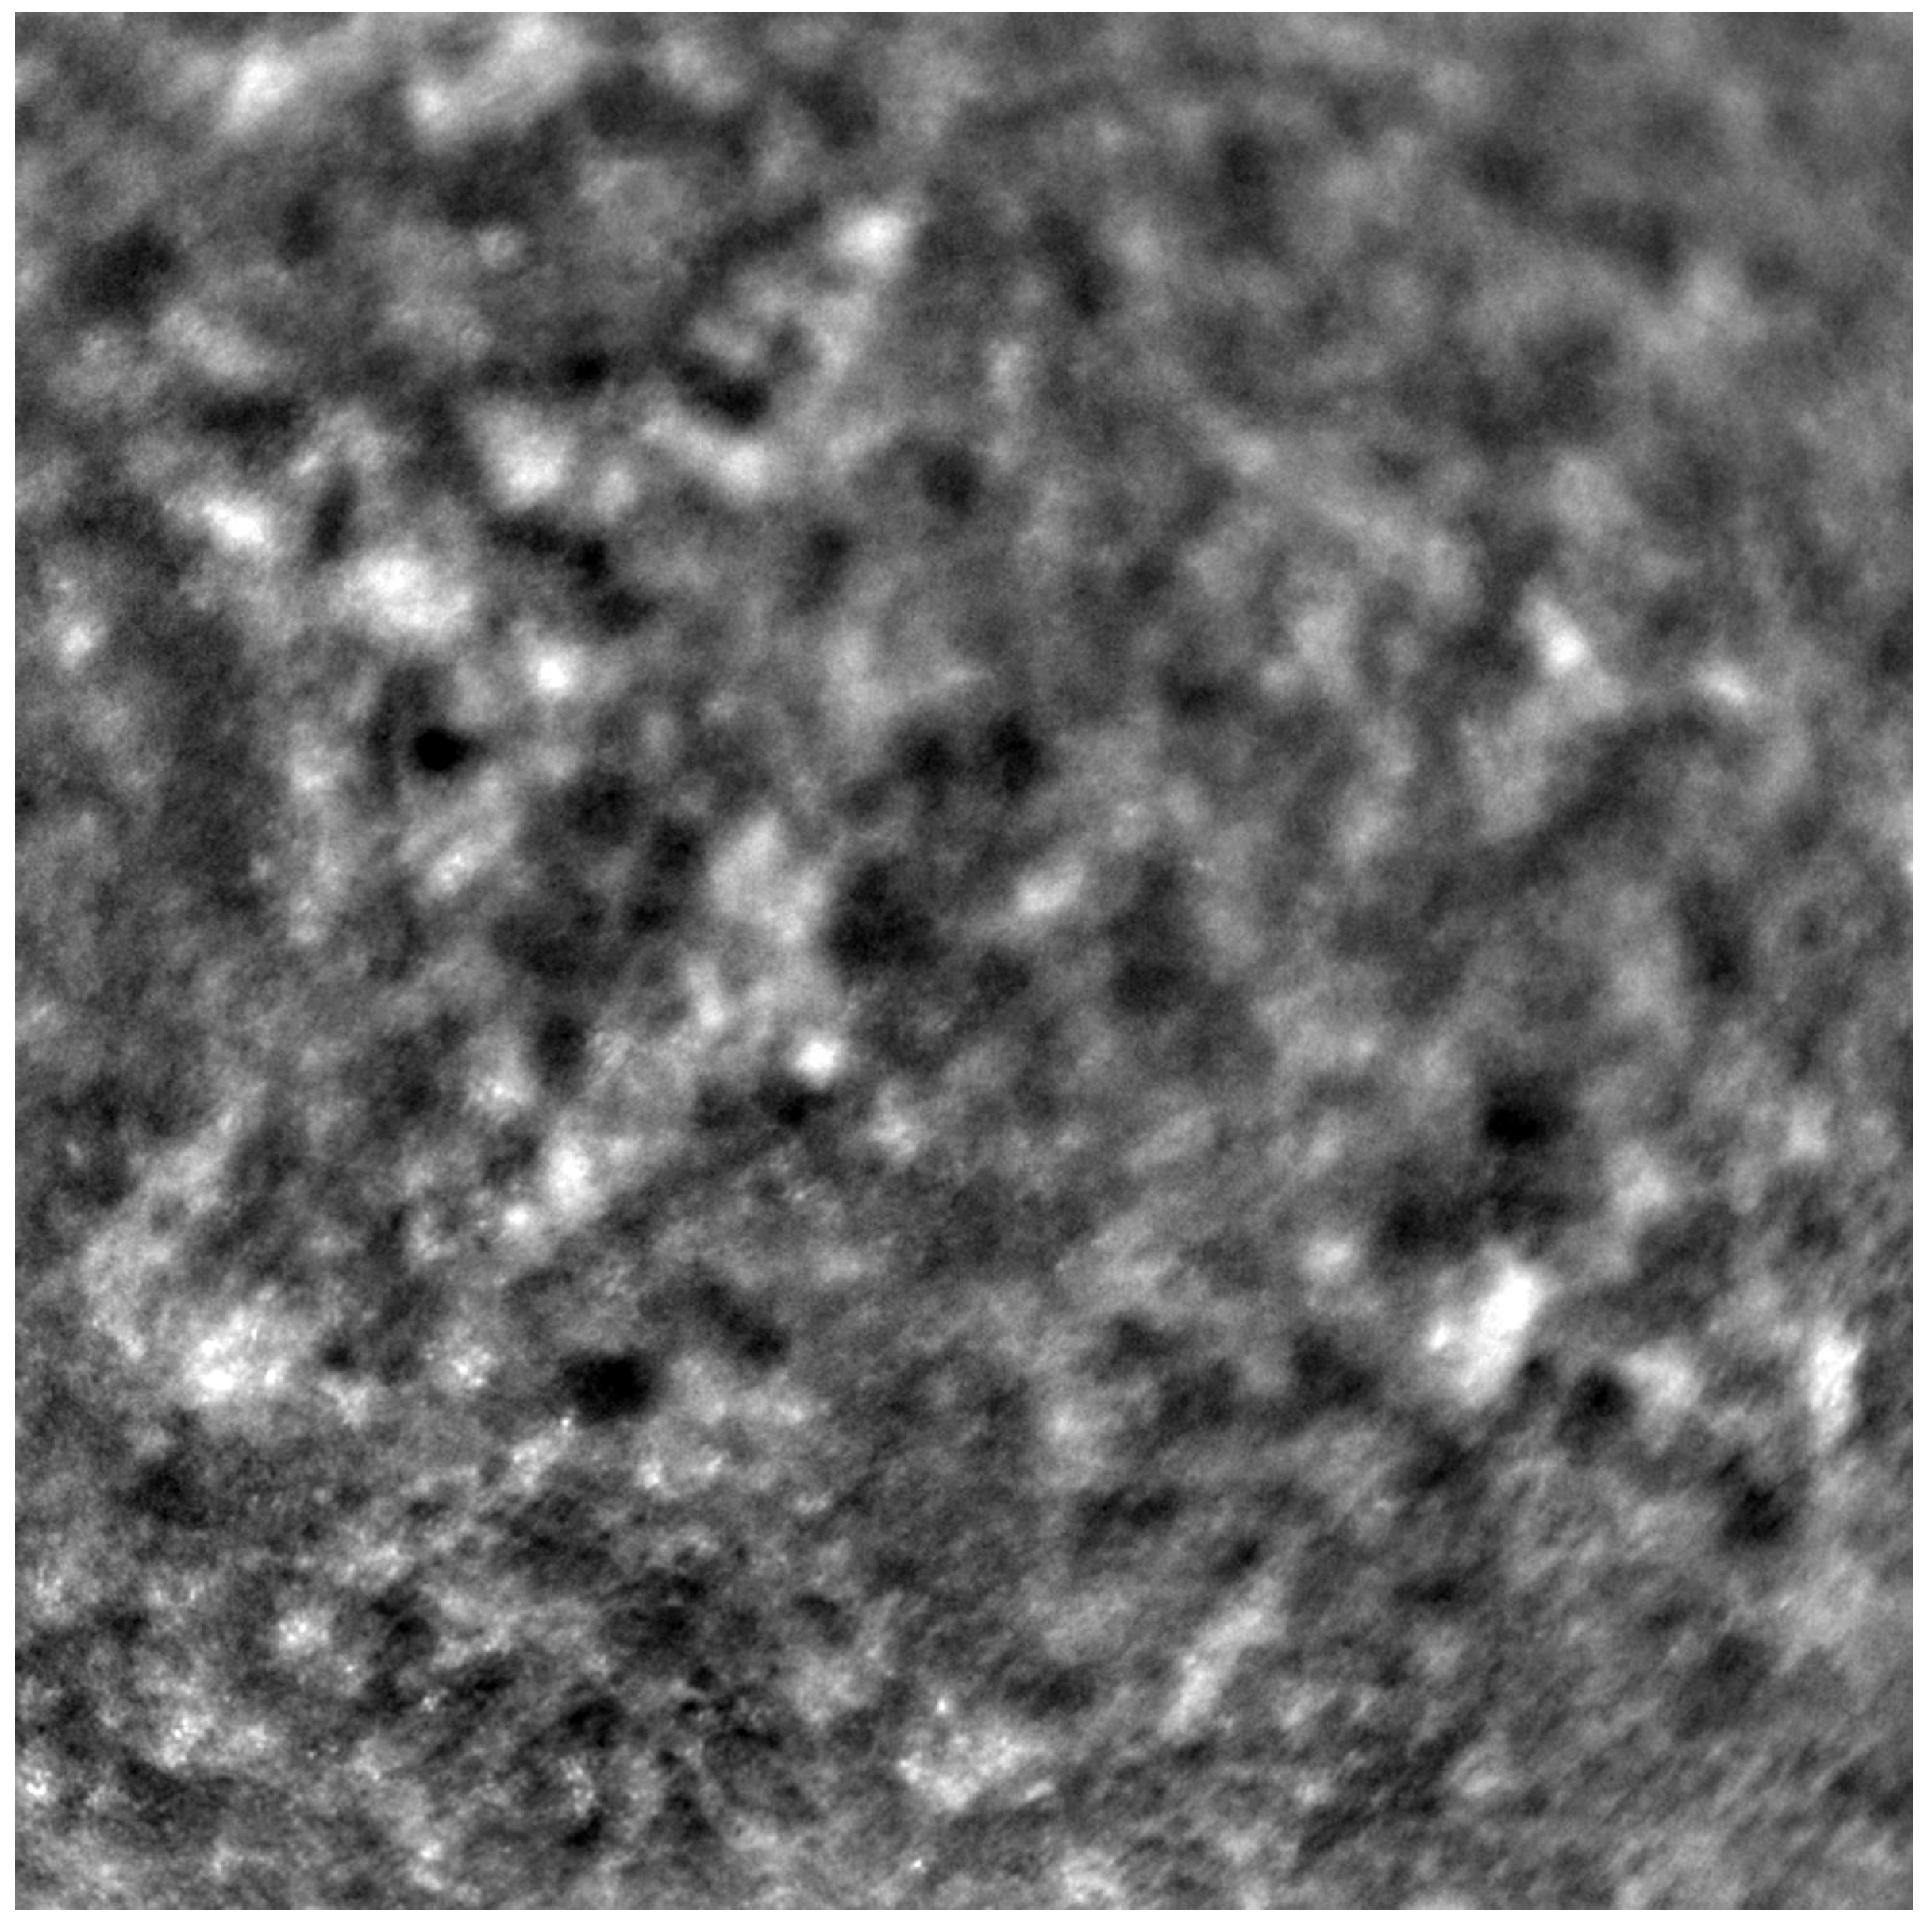

Adaptive optics retinal images depicting a healthy eye, CD, CRD, and STGD are presented in Figure 1, Figure 2, Figure 3 and Figure 4.

Cone mosaic disruption is an abnormality typical of IRDs. The cone and rod spacing is increased in IRDs compared to healthy retinas [18]. Additionally, poor image quality, likely resulting from inadequate fixation in eyes with low visual acuity, is a problem that, in some cases, makes image acquisition impossible [19,20]. In STGD, as well as in other IRDs, the “dark spaces” depicting areas of disrupted cone structure and abnormal cone reflectance have been described [21,22].

Figure 3. An adaptive optics image of photoreceptors in an eye affected by cone–rod dystrophy (Rtx1™, Imagine Eyes, France). Throughout the image, the cones are not clearly visible. Observe the “dark spaces” scattered within the cone mosaic across various regions of the picture.